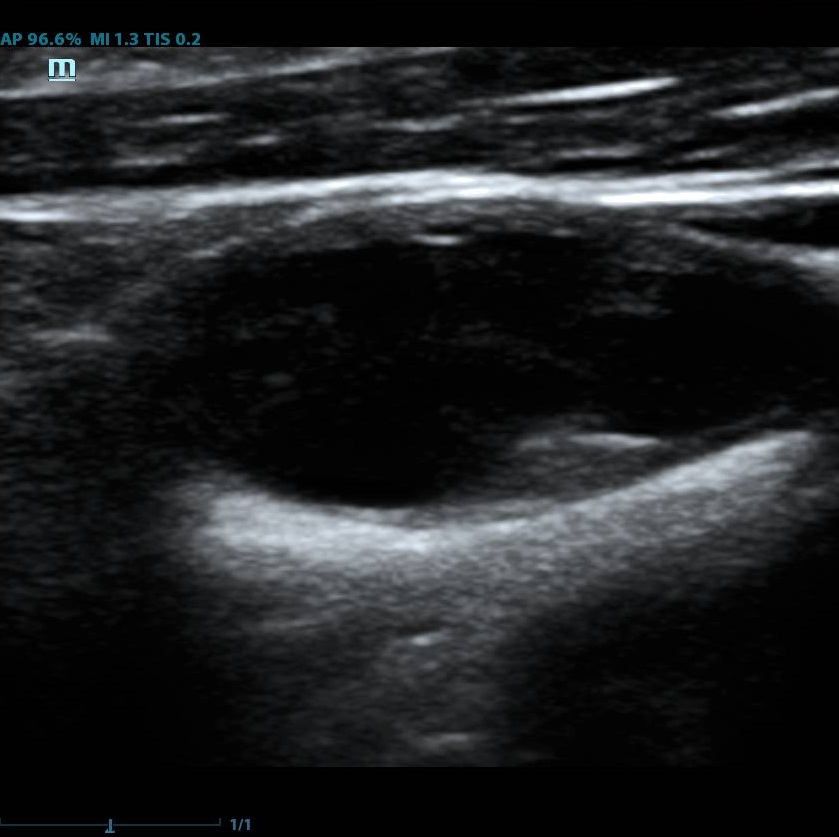

Современное решение – компьютерный анализ структуры бляшки. Ультразвуковая система экспертного класса Mindray DC-8 способна провести программный анализ полученного изображения бляшки и дать количественную оценку её структуры. Для этого используется показатель GSM – Grey Scale Median. Прибор рассчитывает медиану по показателям серой шкалы в выделенной зоне и выдает данные в виде графика распределения эхогенности и числовых данных для количественной оценки. Таким образом, исследование становится более объективным и воспроизводимым, снижается зависимость от оператора (человеческого фактора).